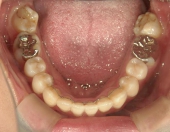

主訴:奥歯で噛んだときに前歯が噛み合わない

高校時代には、歯並びを改善しようと様々な矯正サイトを閲覧し、自分自身が開咬であることを知りました。開咬とは、上下の歯を噛み合わせた時に前歯に隙間ができることを言います。そういえば、麺を前歯で噛みきること、ハンバーガーにガブッと噛みつくことができませんでした。

2年を少し過ぎたころには歯並びが良くなり、開咬もだいぶ改善されました。結婚式を予定していたため早期終了をさせていただきましたが、開咬が治ってハンバーガーをガブッと噛みきることができるようになって、とっても嬉しいです。式でもきれいな歯並びで、思いっきり笑うことができました。

出っ歯や八重歯などの歯並びの悪さばかりが気になっていましたが、開咬には前歯で物が噛みきれない、しゃべるときに息が漏れるなどの症状の他に、奥歯ばかりに負担がかかる為、歯の寿命を縮めてしまう可能性がありました。矯正で改善することができて本当によかっと思います。みなさんも歯並びで気になることがあったら、気軽に相談してみてくださいね。